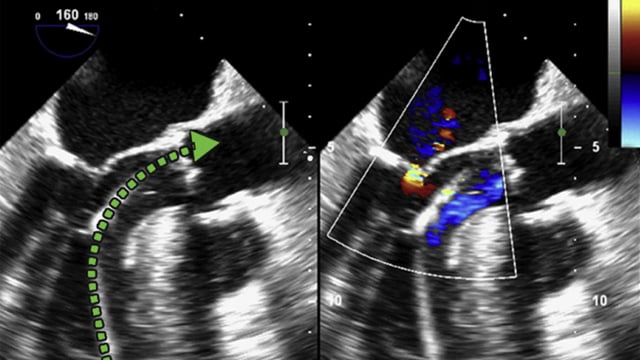

TAVI in bicuspid aortic valve disease - LIVE Case

20 May 2025 – From EuroPCR 2025

A 79-year-old male patient with atrial fibrillation and RBBB on ECG presented with symptomatic severe bicuspid aortic stenosis. LV function was preserved, and coronary artery disease was noted in LAD and first diagonal. A 26 mm Sapien Ultra Resilia valve was implanted via dual femoral access,...